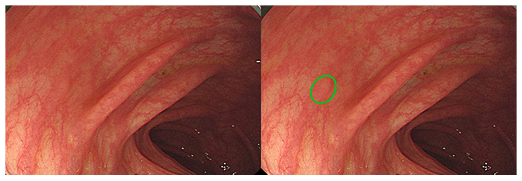

내시경 검사, 이제는 인공지능 내시경이 함께 봅니다.

인공지능 기반 실시간 내시경 영상 분석 시스템으로

의사의 진단을 효율적으로 보조하여 오진을 줄일 수 있도록 도움을 줍니다.

일반 내시경 vs WAYMED ENDO

어려운 위치나 찾기 어려운 주름사이 병변까지,

빠르고 정확하게 병변을 감지합니다.